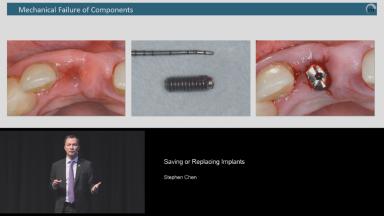

This lecture addresses the decision-making process of whether to save or to remove implant(s) in challenging situations of implant complications. Dr. Chen details incidence and prevalence, options of solving biological, hardware and esthetic complications, and indications of implant removal in each category. Introductions about how to remove the implants and the advantages and disadvantages of each method are also given. Stress is placed on meticulous treatment planning and accurate execution to prevent complications and appropriate management to rectify the complications whenever possible. Attention is given to the factor of clinicians, namely human errors, in the incidence of complications.

understand the etiology of different implant complications

recognize the options to rectify implant complications whenever possible and the limitations